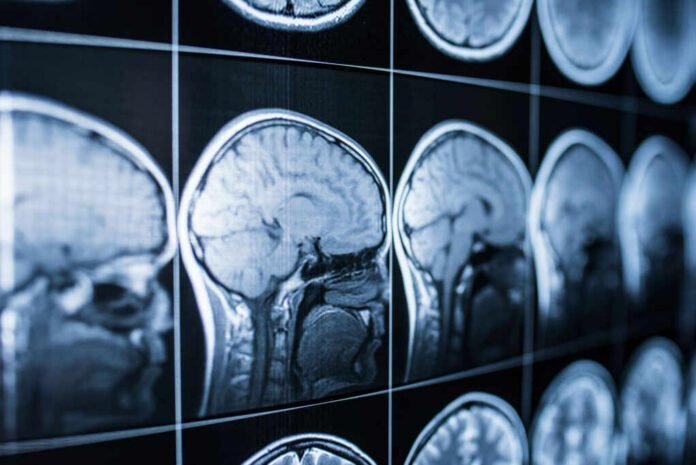

- University of Cambridge researchers analyzed nearly 125,000 women in the UK Biobank, including about 11,000 with MRI scans.

- Post-menopause women showed lower grey matter volume in brain regions tied to memory and emotion, including areas often affected in Alzheimer’s disease.

Researchers at the University of Cambridge, working with the UK Biobank dataset, compared women who were pre-menopause with women who were post-menopause, including those using hormone replacement therapy. The team drew on nearly 125,000 participants and a subset of roughly 11,000 MRI scans to measure brain structure. The core finding was a statistically meaningful reduction in grey matter volume after menopause in specific regions, not a vague “brain fog” anecdote.

The most affected regions included the hippocampus, entorhinal cortex, and anterior cingulate cortex—areas tied to memory formation, information processing, and emotional regulation. That matters because those regions are also commonly discussed in Alzheimer’s research, even though this study does not claim menopause causes Alzheimer’s or that HRT changes Alzheimer’s risk. The work instead maps a biological change that could help explain why many women feel cognitive and emotional disruption.